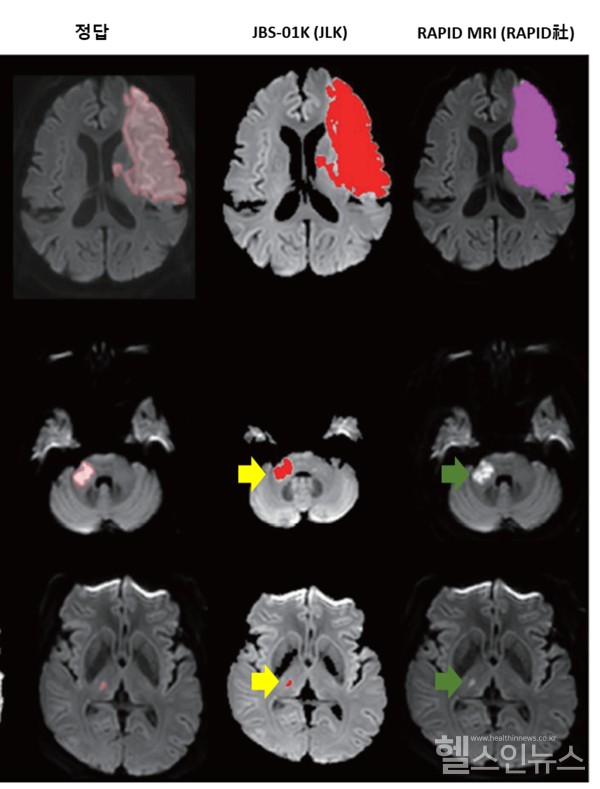

논문에서는 RAPID MRI가 전체 뇌경색 환자의 39%에서만 병변을 검출한 반면 JBS-01K는 98.1%를 검출하여 월등한 성능 차이를 보였다. 특히 전문가도 육안으로 구분이 어려울 수 있는 작은 병변 검출 성능이 월등하였고, 뇌경색 부피 측정에서도 경쟁사 솔루션 대비 5배 더 정확한 성능을 보였다.

최근 뇌경색 환자의 혈관재개통 치료 방향이 더 작은 혈관까지 확장되는 점을 고려하면 JBS-01K의 높은 뇌경색 탐지 및 부피 측정 성능은 촌각을 다투는 응급 상황에서 치료 방침 결정에 결정적 도움을 줄 것을 기대하고 있다고 회사 측은 전했다.